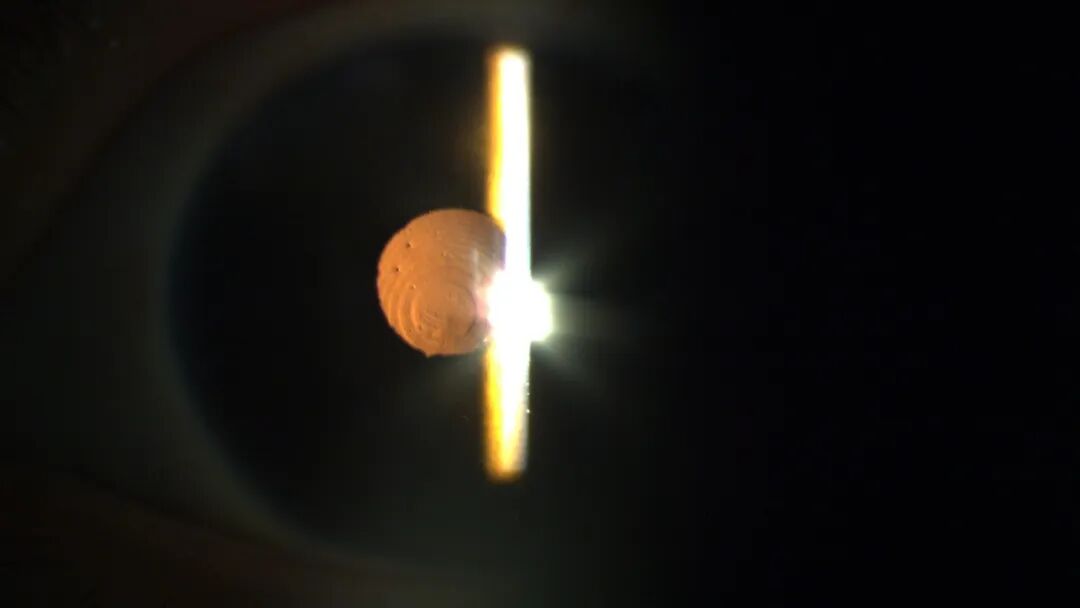

小章术前晶体情况

术前球形晶状体可见边缘(黄色)及松弛悬韧带(黑色)